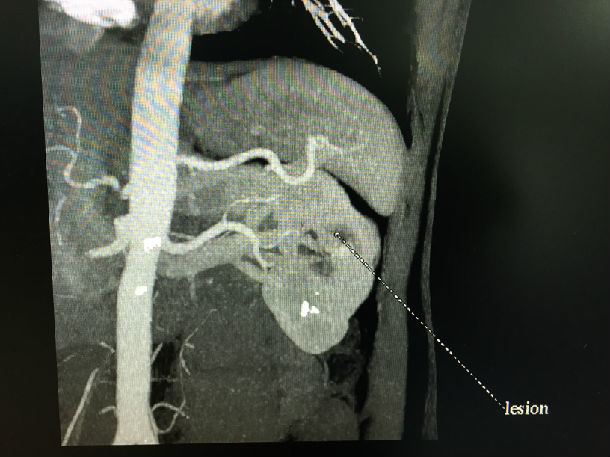

双侧肾肿瘤机器人辅助微创手术成功

中央型肾肿瘤保留肾单位可行吗?

姚旭东 上海第十人民医院